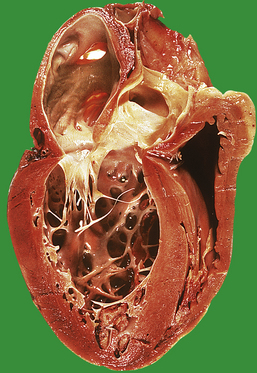

Benign (essential) hypertension

The increased peripheral vascular resistance and cardiac workload associated with hypertension produce left ventricular hypertrophy. During life this can be detected electrocardiographically, and at postmortem there is often substantial concentric thickening of the left ventricle. With the development of congestive cardiac failure, the hypertrophy can be obscured by left ventricular dilatation. Some patients with hypertension also have coronary arterial atherosclerosis and evidence of consequent ischaemic heart disease.